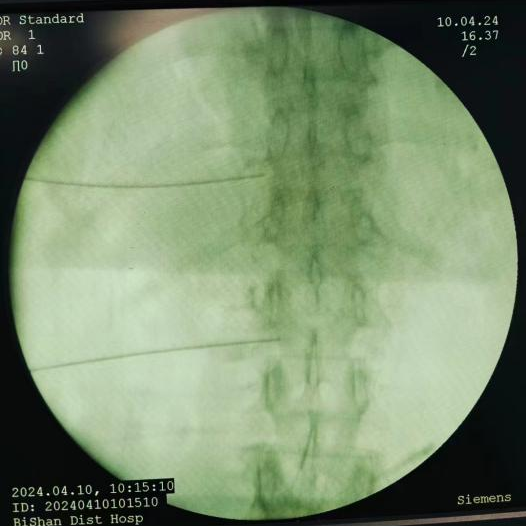

射頻調(diào)控技術(shù):通過脈沖射頻調(diào)節(jié)神經(jīng)功能,阻斷疼痛信號傳導(dǎo),治療帶狀皰疹后神經(jīng)痛,具有微創(chuàng)、安全、恢復(fù)快的優(yōu)點(diǎn)。

圖片

帶狀皰疹性神經(jīng)痛射頻調(diào)控術(shù)